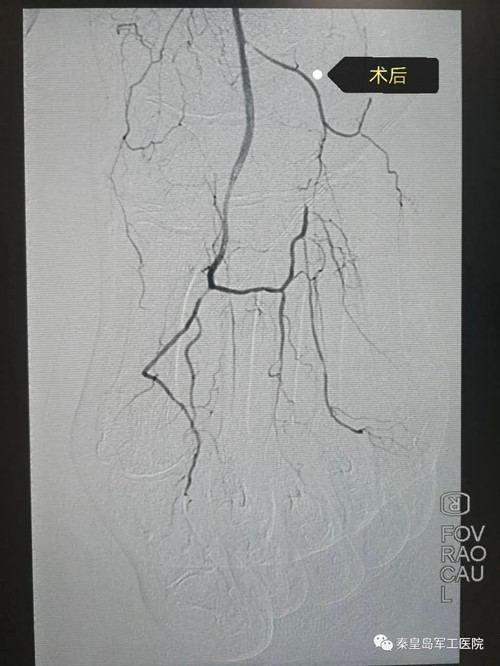

患者基础疾病平稳后,张杨副主任对患者进行左下肢动脉造影术、左下肢动脉支架植入术及球囊扩张术。术中导丝携球囊到达足背动脉及足弓动脉并且成功扩张时,在场所有医护人员为之高兴,这只脚保住了。

术后患者左足疼痛明显缓解,股浅动脉、腘动脉、胫前动脉、腓动脉、足背动脉、跖趾背动脉成功开通。下一步,张主任根据患者左足坏疽具体情况,继续创面续贯治疗。